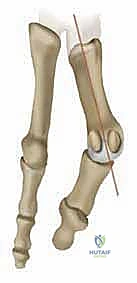

* انحراف العظمة المشطية الأولى: تبدأ العظمة المشطية الأولى (العظمة الطويلة التي تسبق الإبهام) بالانحراف نحو الداخل (باتجاه القدم الأخرى).

* انحراف السلامية (الإبهام): كرد فعل، ينحرف إصبع الإبهام نفسه نحو الخارج (باتجاه الأصابع الصغيرة للقدم).

* بروز المفصل: هذا الانحراف المتعاكس يؤدي إلى بروز رأس العظمة المشطية الأولى، مكوناً الكتلة العظمية المؤلمة التي نراها من الخارج.

* الزاوية المفصلية المشطية البعيدة (DMAA): في الحالات المتقدمة، يتشوه سطح المفصل نفسه ويميل بزاوية غير طبيعية. الجراحات التقليدية تفشل في علاج هذه الزاوية، وهنا تبرز أهمية تقنية شفرون ثنائية المستوى التي يطبقها الدكتور هطيف لتصحيح هذه الزاوية بدقة متناهية.